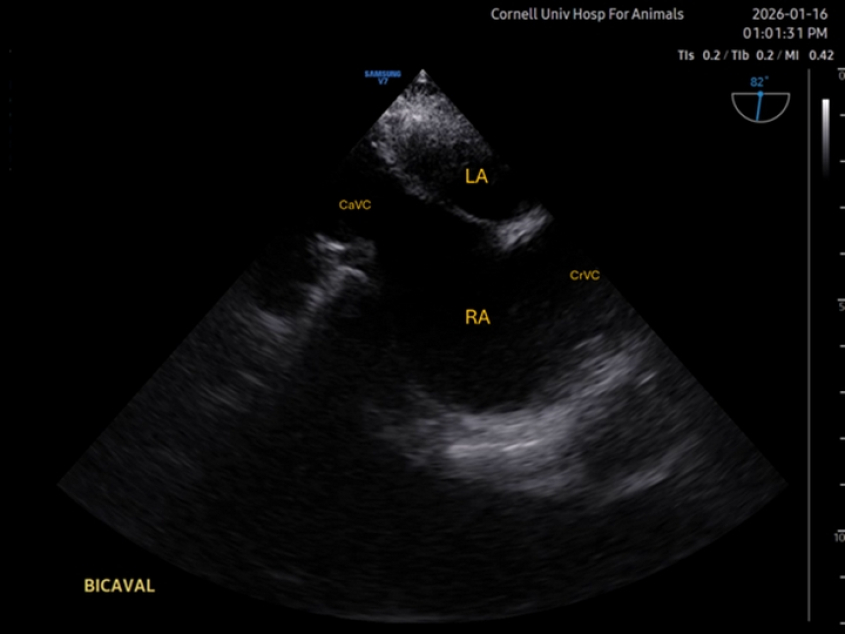

Mid-esophageal Bicaval

The bicaval view shows the left atrium in the near field, and right atrium in the center. The interatrial septum can be observed. Ideally, both cranial and caudal caval veins (CrVC and CaVC) are in view also. The view might be useful for assessing venous return or collapse of the right atrium in cases of tamponade. Additionally, placement of central catheters can be guided with this view. The view is not always easy to acquire. Typically, starting from a ME 4C view centered at the right atrium, or from a short axis of the aortic valve (both with the omniplane at 0°), rotation of the omniplane to 80-110° is applied.